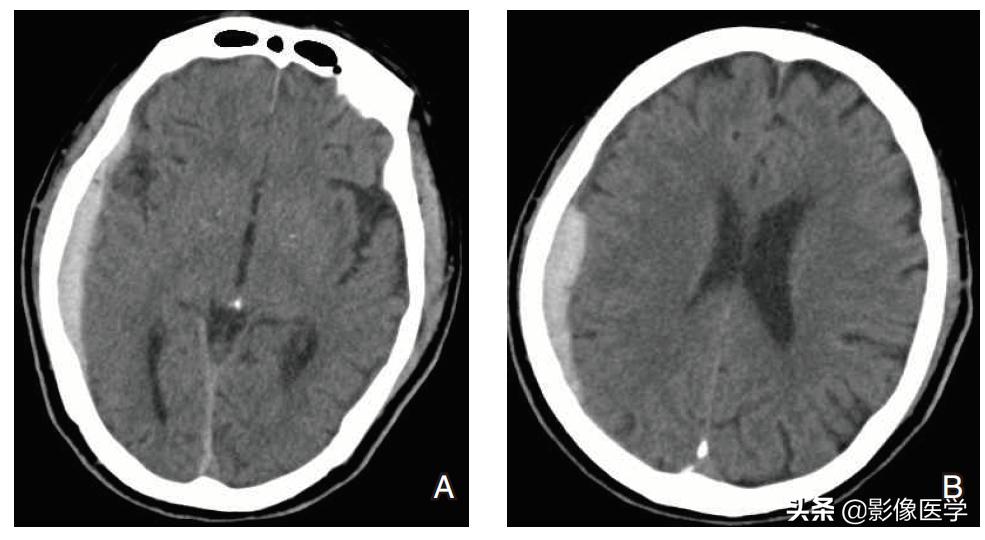

case 1

【病史】男性,4岁。头部外伤。

【影像学检查】头颅CT检查:

【影像学表现】头颅CT平扫(图A、B)示右侧颞顶部颅骨内板下见新月状密度增高影,邻近脑实质轻度受压、内移。

【影像学诊断】右侧颞顶部急性硬膜下血肿。

【最后诊断】右侧颞顶部急性硬膜下血肿。